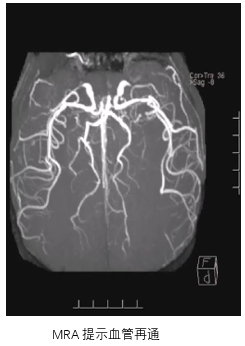

• 术后一天:DWI显示梗塞面积没有明显增大,MRA提示血管再通,发现存在LMCA动脉瘤。